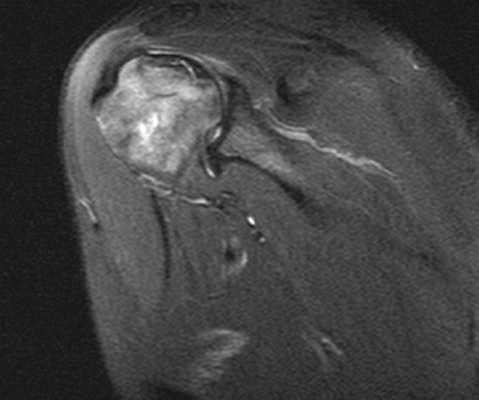

МРТ плечевого сустава, что показывает?

МРТ плечевого сустава

Нативное МРТ досконально отражает анатомию плечевого сустава. Исследование с контрастированием позволяет выявить мельчайшие очаги воспаления, опухоли и нарушения кровообращения.

МРТ плеча

Расшифровка фото снимков МРТ плечевого сустава

Результатом МР-сканирования являются послойные изображения исследуемой области в трех, взаимноперпендикулярных проекциях. Анализом фото занимается врач-рентгенолог, который фиксирует и описывает любые отклонения структуры сустава от нормы.